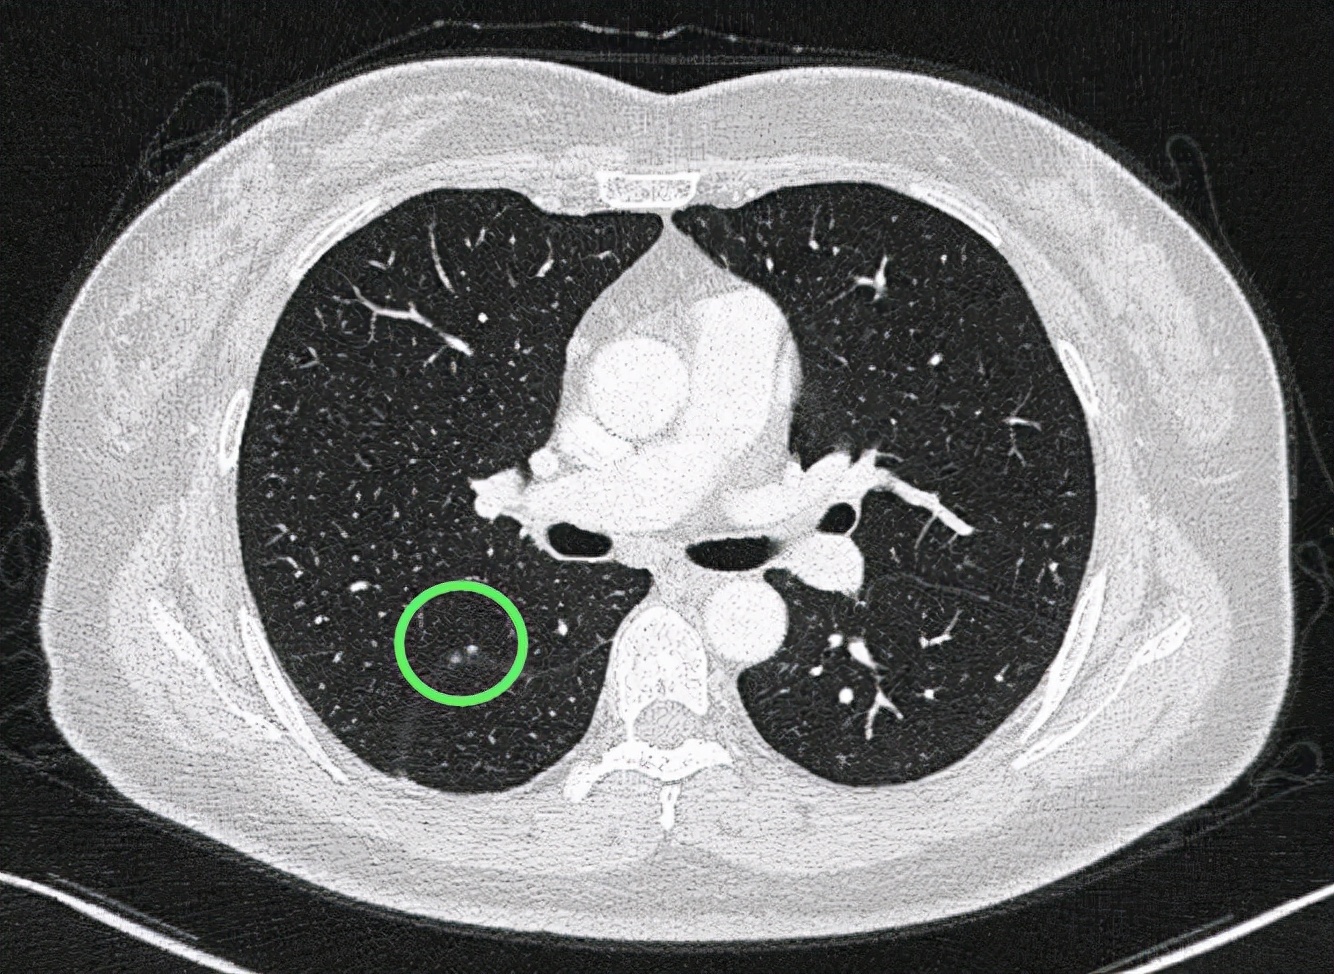

斜裂处微小实性结节

水平裂处多发微小实性结节,小而密度高